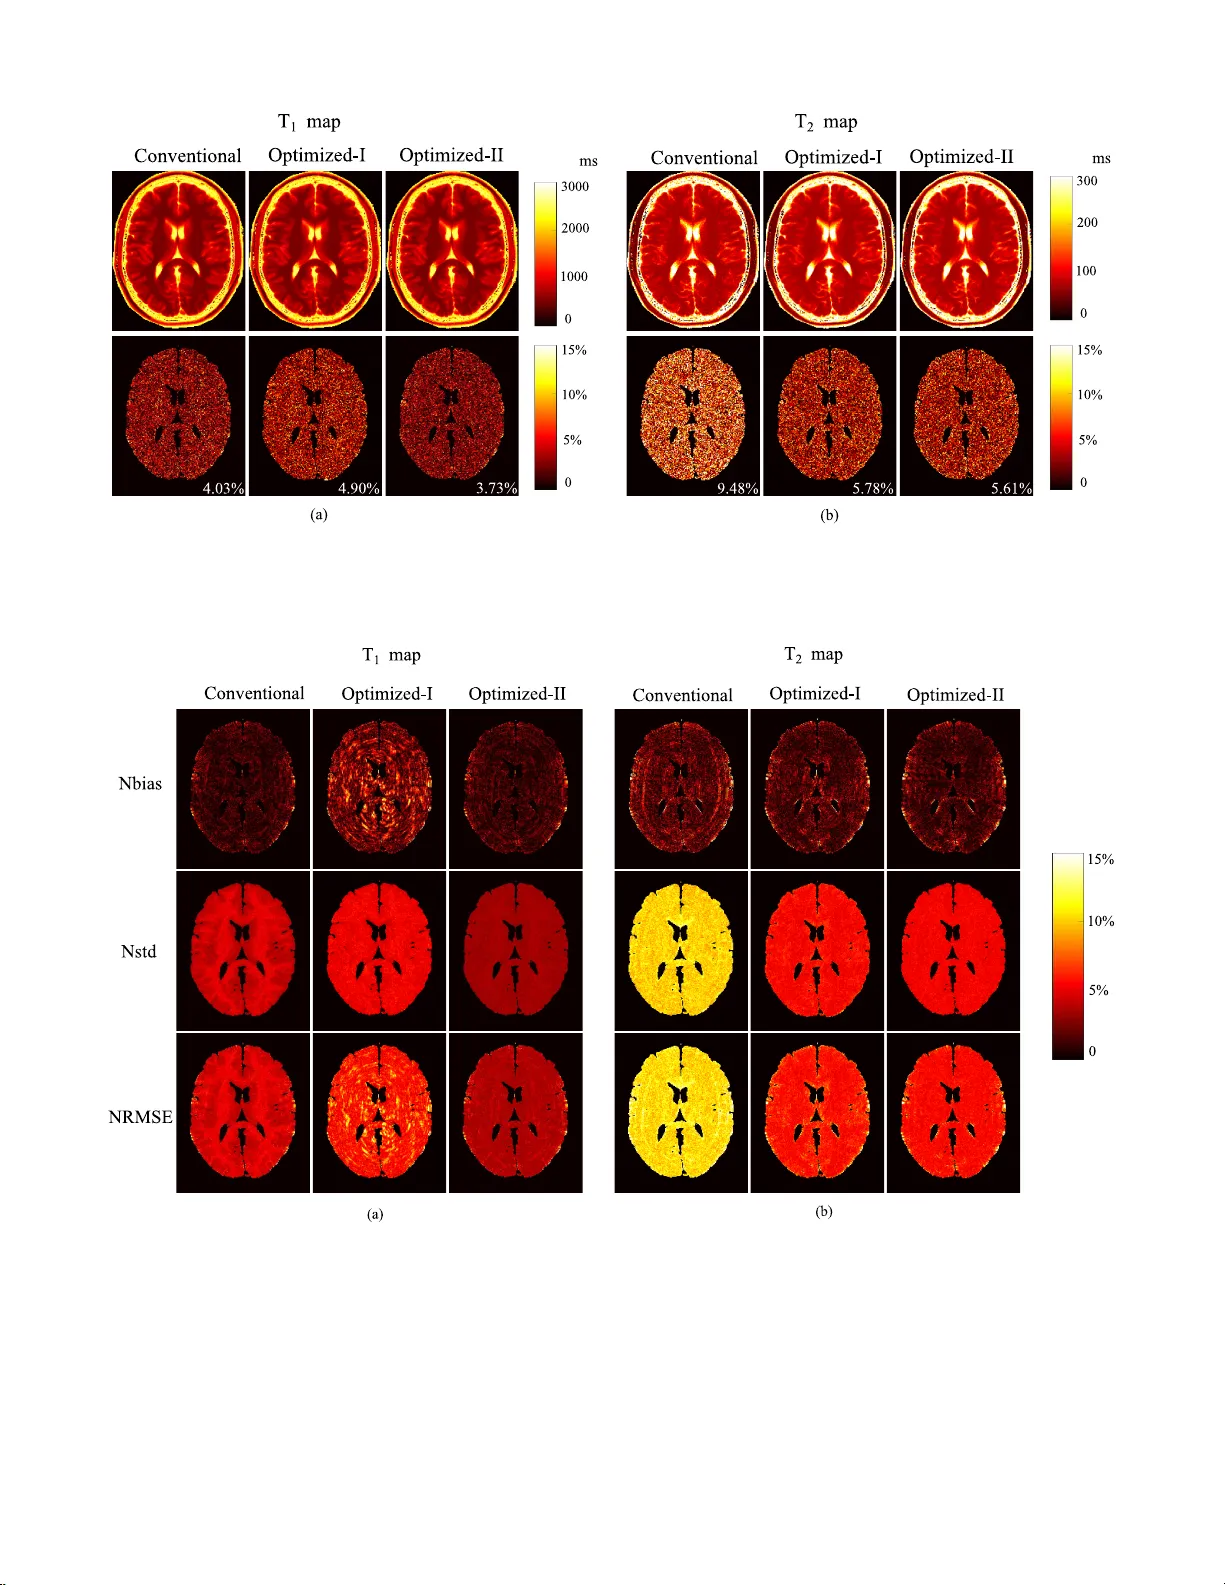

본 논문은 자기공명지문(MRF) 실험을 위한 최적 설계 프레임워크를 제시한다. 이론적으로 스핀 동역학을 이산시간 상태공간 모델로 표현하고, 크래머‑라오 한계(CRB)를 이용해 신호‑대‑잡음비(SNR) 효율을 정량화한다. CRB를 목적함수로 하는 최적화 문제를 풀어 플립각, 반복시간(TR), 에코시간(TE) 등 획득 파라미터의 시퀀스를 설계하고, 물리적·재구성 제약을 동시에 만족시킨다. 시뮬레이션·팬텀·인체 실험을 통해 최적 설계가 기존 무작위 …

본 논문은 자기공명지문(Magnetic Resonance Fingerprinting, MRF)이라는 최신 정량적 MRI 기법의 실험 설계 문제를 체계적으로 해결하고자 한다. MRF는 하나의 스캔에서 T₁, T₂, 프로톤 밀도 등 여러 조직 파라미터를 동시에 추정할 수 있는 장점이 있지만, 기존 구현에서는 플립각, 반복시간(TR), 에코시간(TE) 등을 무작위 혹은 준무작위로 변조하는 방식을 사용해 왔다. 이러한 설계는 직관적으로 다양한 신호 변화를 유도한다는 점에서 채택되었지만, 실제로 파라미터 추정 효율을 최적화한다는 근거는 부족했다. 저자들은 이 문제를 “어떻게 하면 주어진 측정 시간과 하드웨어 제약 하에 파라미터 추정 정확도를 최대화할 수 있는가”라는 질문으로 재정의하고, 이를 해결하기 위해 두 가지 핵심 이론을 결합한다. 첫 번째는 스핀 동역학을 이산시간 상태공간 모델로 표현하는 것이다. Bloch 방정식은 연속시간 미분 방정식이지만, MRF는 각 반복(TR)마다 신호를 샘플링한다. 따라서 저자들은 각 반복을 하나의 시간 단계로 보고, 플립각·위상·TR·TE 등 획득 파라미터를 입력 u